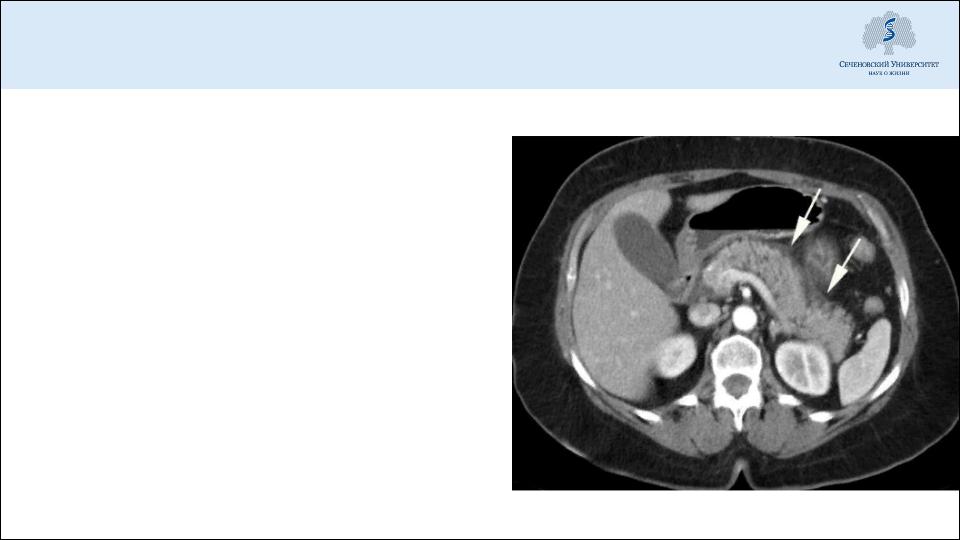

Диагностика: компьютерная томография

Выявление некрозов, их распространенности

Выявление местных осложнений панкреатита

Оптимальный срок выполнения – 72 ч от начала заболевания (время формирования некрозов)

При тяжелом остром панкреатите (панкреонекрозе) – динамическая КТ (раз в 4-7 дней) для контроля воспалительного процесса, изменений в поджелудочной железе, забрюшинной клетчатке etc.